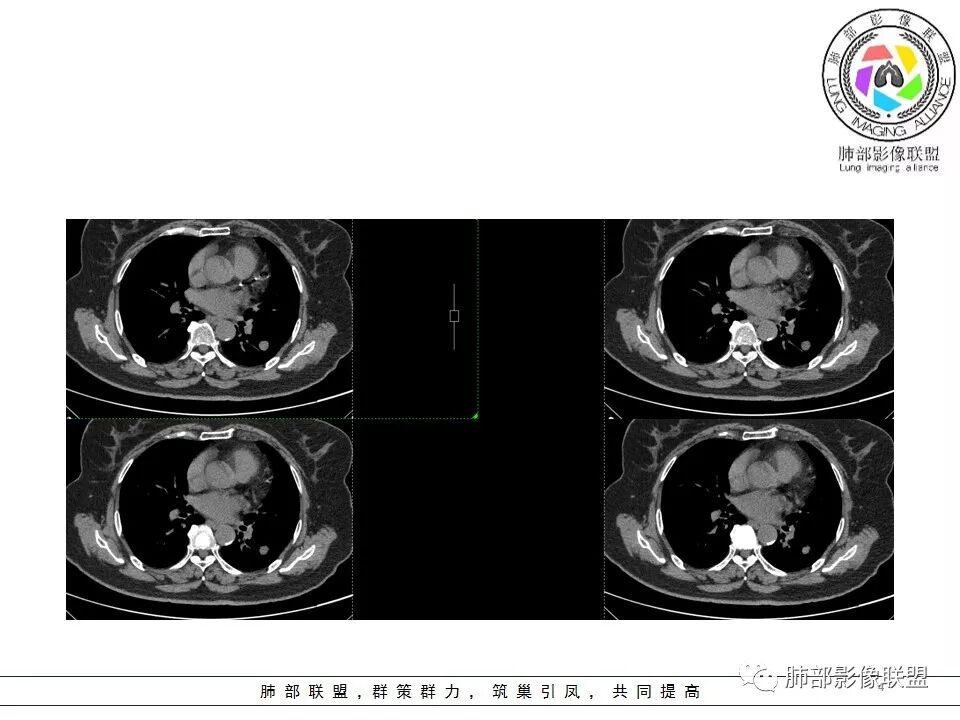

病例资料

群内讨论

体检发现左肺占位,类圆形,无分叶,毛刺等,增强后有贴边血管,考虑硬化性肺细胞瘤。

体检发现肺部结节。

胸CT:左下肺实性结节,密度均匀,边缘光滑,未

毛刺、分叶、晕征及棘突样改变,增强可见血管贴边,静脉期较动脉期强化。

诊断:PSP

鉴别:肉芽肿性病变。